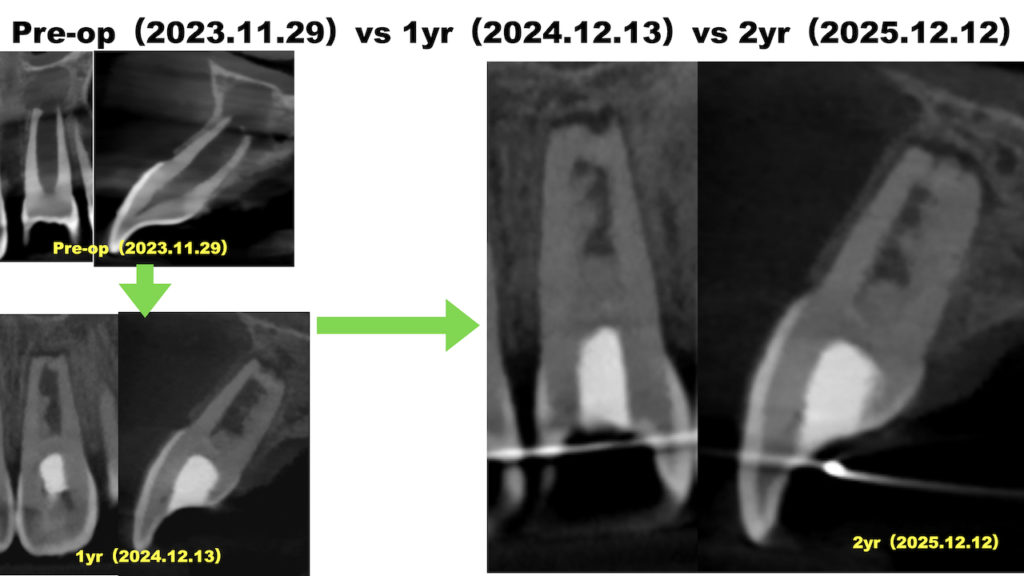

9歳児の歯科治療〜#9 Regenerative Endodontics 2回法 2yr recall

以前の治療の経過観察。 治療から2年が経過した。 9歳児の歯科治療〜#9 Regenerative Endodontics 2回法 9歳児の歯科治療〜#9 Regenerative Endodontics 2回法 1yr … 続きを読む 9歳児の歯科治療〜#9 Regenerative Endodontics 2回法 2yr recall